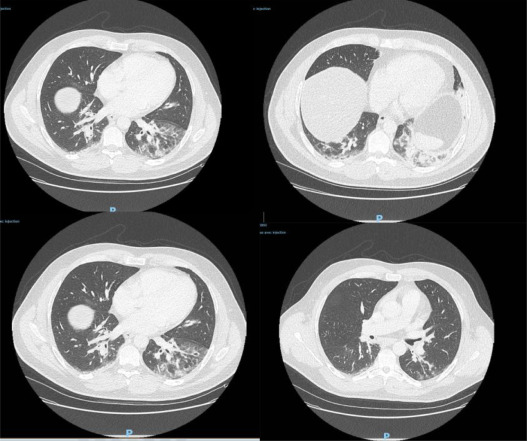

“Durante el período de estudio, 14 (24%) de 58 pacientes ingresados por ILI se incluyeron en el análisis actual. Una muestra tomada de un hombre desempleado de 42 años nacido en Argelia que había vivido en Francia durante muchos años fue positivo. Su último viaje al extranjero fue a Argelia en agosto de 2019. Uno de sus hijos se presentó con ILI antes del inicio de sus síntomas. Su historial médico incluía asma y diabetes mellitus tipo II. Se presentó a la sala de emergencias el 27 de diciembre de 2019 con hemoptisis, tos, dolor en el pecho, dolor de cabeza y fiebre, evolucionando durante 4 días. El examen inicial no fue notable y la tomografía computarizada (TC) de tórax reveló opacidades pulmonares bilaterales en los lóbulos inferiores”

“Aquí informamos una observación de un paciente infectado con SARS-CoV-2 1 mes antes de los primeros casos reportados en Francia. Al ingreso, el paciente presentaba signos clínicos y patrones radiológicos frecuentemente observados previamente en enfermos de China e Italia. La identificación del primer paciente infectado es de gran interés epidemiológico, ya que cambia drásticamente nuestro conocimiento sobre el SARS-CoV-2 y su propagación en el país. Además, la ausencia de un vínculo con China y la falta de viajes recientes al extranjero sugieren que la enfermedad ya se estaba extendiendo entre la población francesa a fines de diciembre de 2019.”